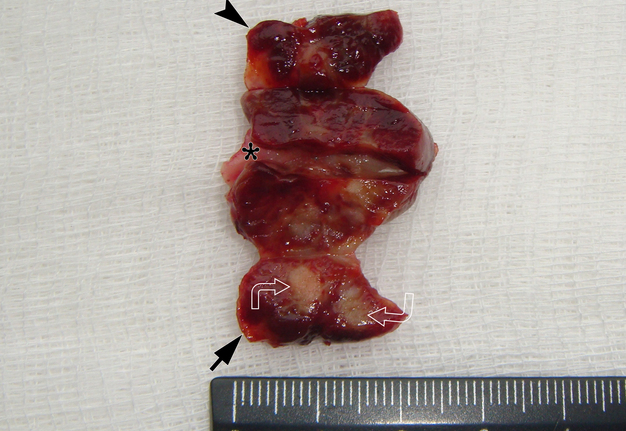

It is worth noting the mushroom-shaped appearance of the lesion, which had an extremely large saddle-shaped “cap” and an extremely thin “stem/stipe.” After removal, when the gross specimen was cut, several areas with calcifications were found (Fig 7). It felt as if the cartilage tissue was being cut when cutting specimen in areas of calcifications.

FIGURE 7A. Macroscopic view of the lesion. Image A shows a top view of the lesion. Image B shows the removed saddle-shaped lesion in inverted position, which clearly demonstrates its shape. Arrow labels anterior (vestibular) lobe and arrowhead labels posterior (lingual) lobe of this lesion. The attachment zone is indicated by an asterisk. The gross specimen after a longitudinal section (C) and subsequent two separate sections (D) of the anterior (arrow) and posterior (arrowhead) lobes of the lesion shows presence of calcified areas (open arrows).

FIGURE 7B. Macroscopic view of the lesion. Image A shows a top view of the lesion. Image B shows the removed saddle-shaped lesion in inverted position, which clearly demonstrates its shape. Arrow labels anterior (vestibular) lobe and arrowhead labels posterior (lingual) lobe of this lesion. The attachment zone is indicated by an asterisk. The gross specimen after a longitudinal section (C) and subsequent two separate sections (D) of the anterior (arrow) and posterior (arrowhead) lobes of the lesion shows presence of calcified areas (open arrows).

FIGURE 7C. Macroscopic view of the lesion. Image A shows a top view of the lesion. Image B shows the removed saddle-shaped lesion in inverted position, which clearly demonstrates its shape. Arrow labels anterior (vestibular) lobe and arrowhead labels posterior (lingual) lobe of this lesion. The attachment zone is indicated by an asterisk. The gross specimen after a longitudinal section (C) and subsequent two separate sections (D) of the anterior (arrow) and posterior (arrowhead) lobes of the lesion shows presence of calcified areas (open arrows).

FIGURE 7D. Macroscopic view of the lesion. Image A shows a top view of the lesion. Image B shows the removed saddle-shaped lesion in inverted position, which clearly demonstrates its shape. Arrow labels anterior (vestibular) lobe and arrowhead labels posterior (lingual) lobe of this lesion. The attachment zone is indicated by an asterisk. The gross specimen after a longitudinal section (C) and subsequent two separate sections (D) of the anterior (arrow) and posterior (arrowhead) lobes of the lesion shows presence of calcified areas (open arrows).